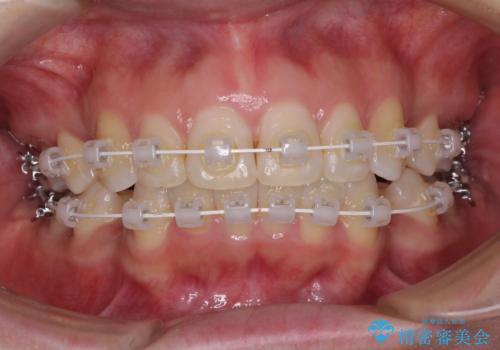

- 矯正装置

- インビザライン・審美装置

2年ほどインビザラインを使用しましたが、どうしても歯の移動がマウスピースに追随せず、全顎ワイヤー矯正へ切り替えました。

ワイヤー装着後は2年弱で、しっかりと仕上げることができました。